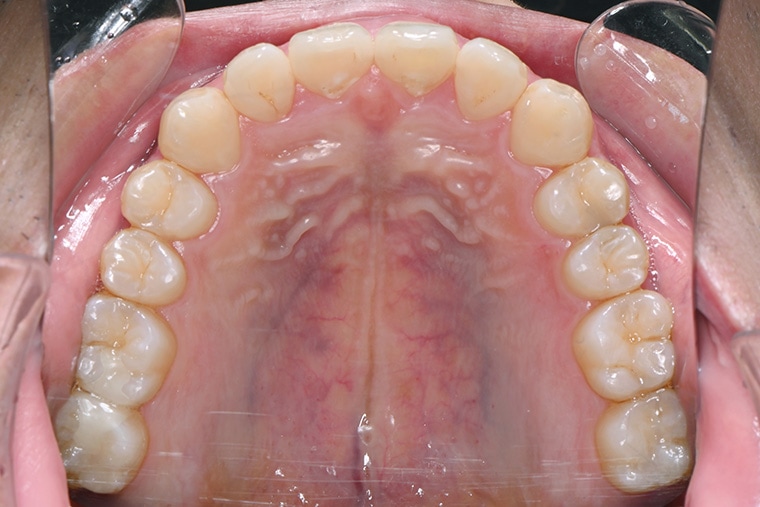

Case Study26歳男性出っ歯のマウスピース矯正-矯正期間8ヶ月(2023年11月開始)